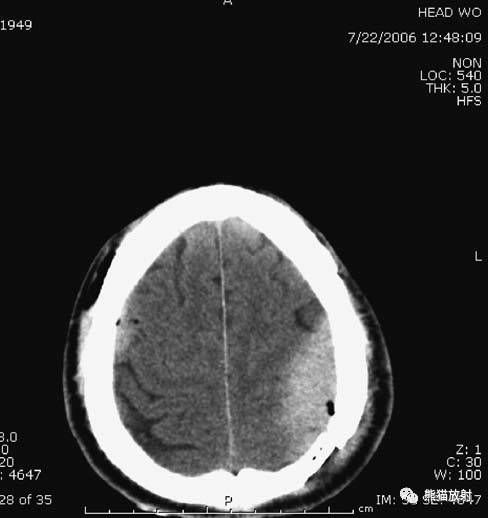

3、硬膜下血肿

右侧硬膜下血肿(急性-高密度,慢性-低密度);右侧大脑水肿,中线结构移位。